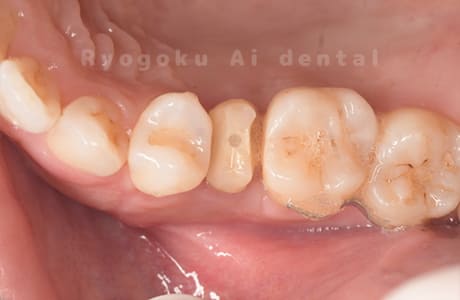

Case12

- 縁下カリエス

- 治療内容

- クラウンレングスニング、ジルコニアクラウン修復

- 治療費用

- 約220,000円

被せ物の中から臭いがするとのことで、被せ物を外したところ大きな虫歯となっていました。このまま被せてしまうと被せ物が外れやすいため、埋まっている歯を出すためのクラウンレングスニング処置を行い、その後、ジルコニアクラウンで被せ物を行いました。